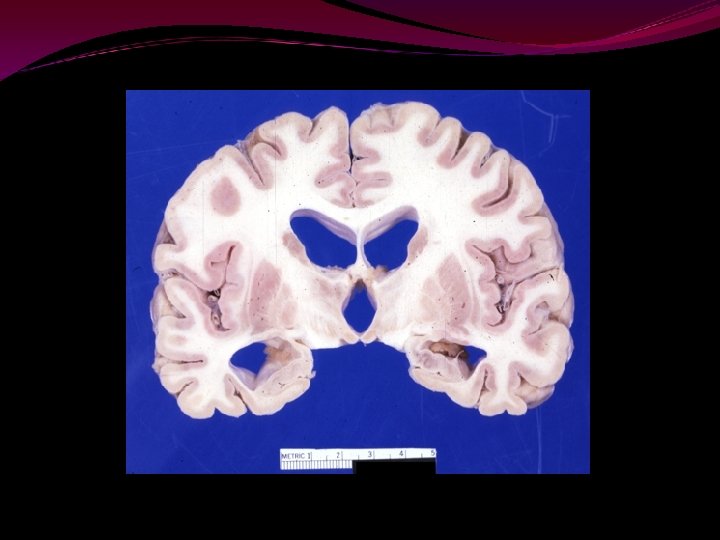

Hippocampal atrophy is a highly sensitive indicator of incipient AD. It's evaluation by MRI volumetry provides entirely additional data to support the diagnosis. In contrast, simpler measurements or T 2 relaxometry provided only little diagnostic aid. The volume of the hippocampus correlated significantly with clinical severity assessed by MMSE, and with tests assessing delayed recall, which is considered to be affected early in dementia and may reflect hippocampal dysfunction. 2. The volume of the hippocampus is not significantly affected by normal aging. AAMI can be differentiated from dementia by hippocampal volumetry